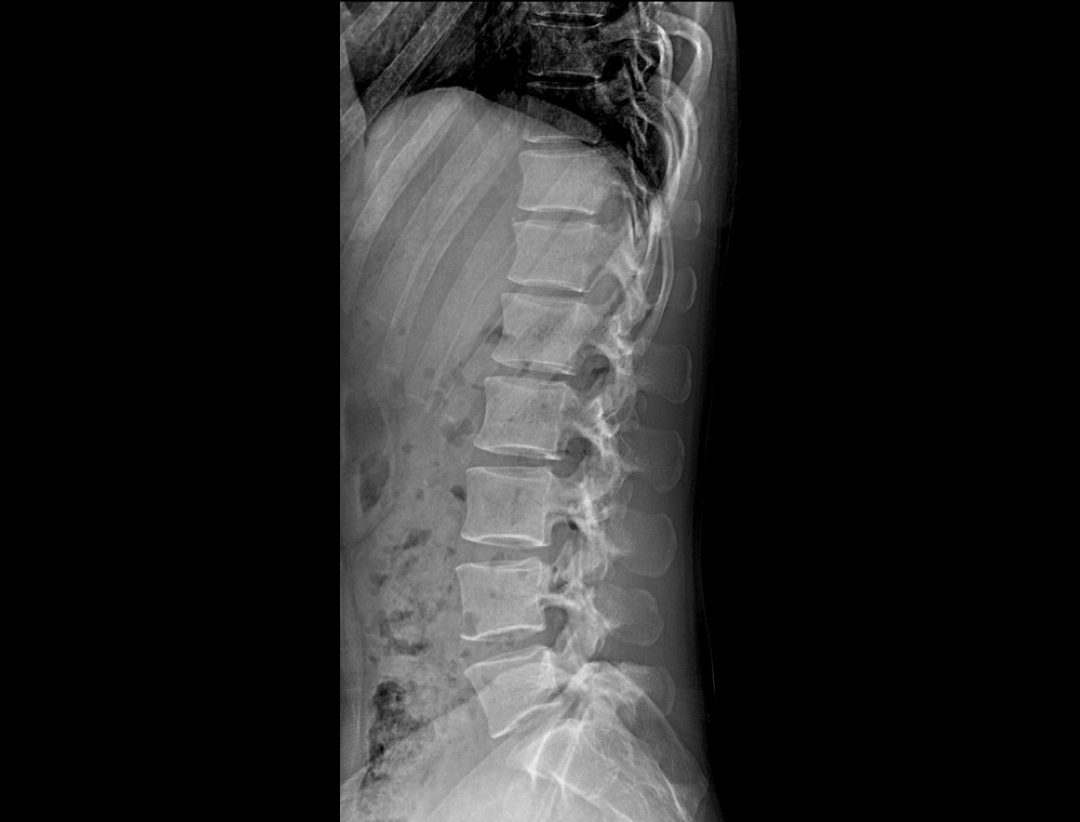

自动拍摄拼接,一气呵成

智能全景成像

全自动无尺全景拼接*

支持自动立位无尺全景拼接,为骨科、整形外科提供高质量全景影像。